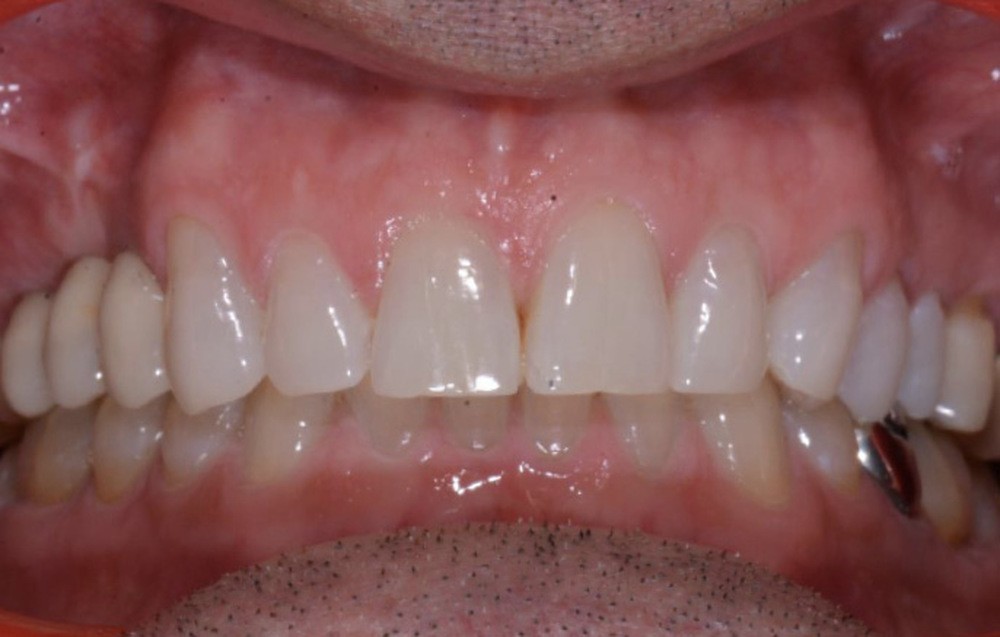

Présentation du cas clinique (fig. 1 à 3)

Le patient, âgé de 58 ans, présente un encombrement dentaire mandibulaire de 5 mm dans un contexte squelettique hypodivergent.